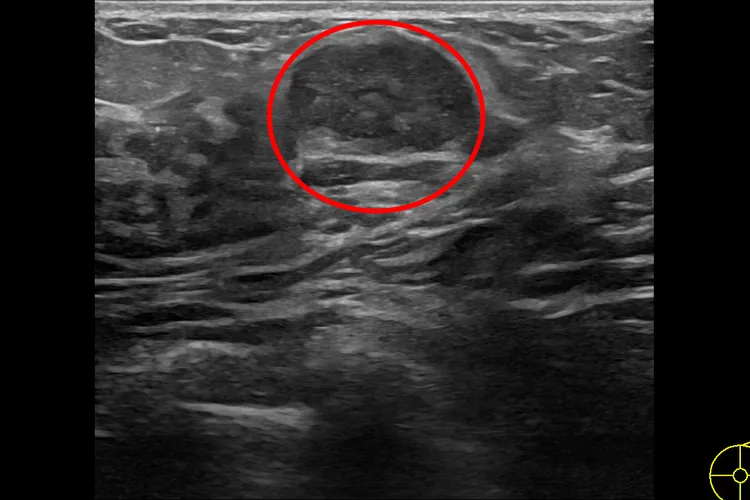

慈濟乳房醫學中心主任張群明醫師表示,「年輕女性做自我乳房觸檢時所摸到的腫塊,大部分為良性的乳房腫瘤,其中以乳房纖維瘤最常見。」乳房纖維瘤是從乳房小葉組織長出並混合上皮與間質組織增生的腫瘤,常見於14 到35 歲年輕女性,發生率約10-20%;纖維瘤摸起來較平滑,有時會有輕微的壓痛,在超音波影像顯示上,是邊界清楚的圓形或橢圓形的腫瘤。

良性乳房纖維瘤。花蓮慈濟醫院提供